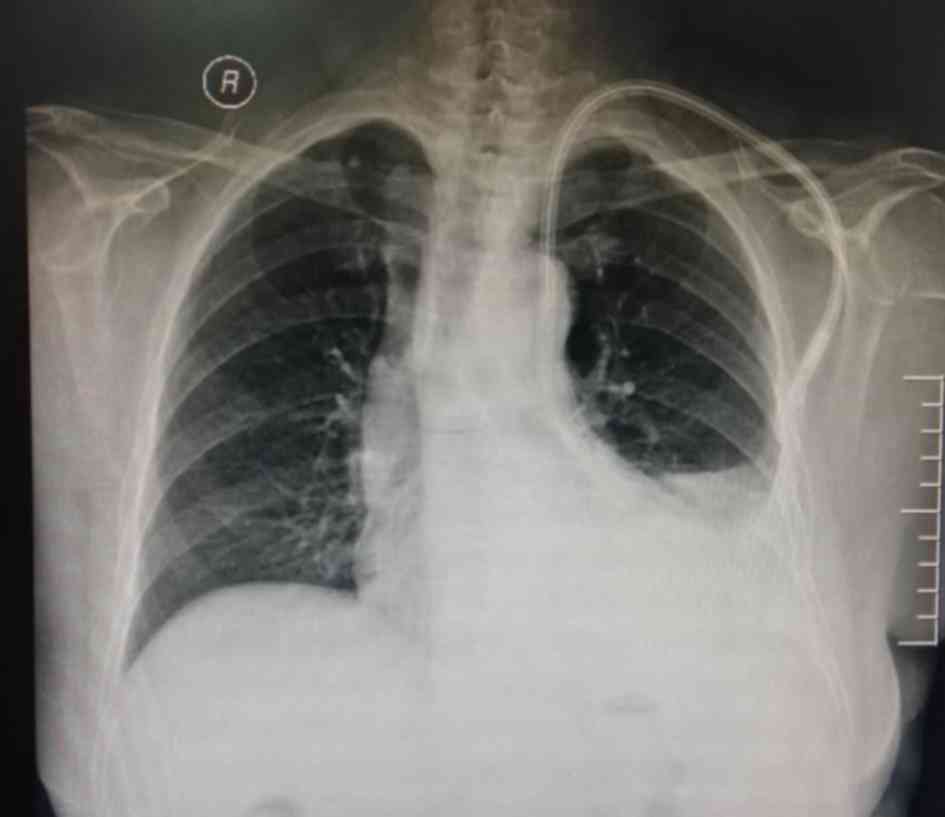

The present study reported a case of left BCV perforation that was diagnosed at the First Affiliated Hospital of the University of Science and Technology of China (USTC; Hefei, China). The present study was approved by the Ethics Committee of The First Affiliated Hospital of the USTC and informed consent was also obtained from the patient. A 64-year-old female with a 15-year history of hypertension underwent left forearm arteriovenous fistula (AVF) surgery to treat stage-V chronic kidney disease (CKD) five years previously. One month prior to presentation at our department on June 8, 2017, the patient had a fistula obstruction and a local hospital placed a temporary catheter in the patient's right femoral vein for hemodialysis. However, the inserted catheter caused occlusion of the right BCV. Review of the patient's medical history revealed that she received a long-term hemodialysis catheter (hemosplit 14.5F/23 cm; BARD) via the left internal jugular vein (LIJV) two days prior to occurrence of HS. LIJV punctures using the Seldinger technique were performed under local anesthesia, followed by smooth introduction and positioning of the guidewires in the left IJV to a level just below the diaphragm. After dilator and guidewire removal, the catheters were introduced, followed by removal of the peel-away sheaths. When placing the catheters, the surgeon felt a marked resistance. Furthermore, the patient reported mild pain and discomfort in the left chest during the catheterization process. After the completion of catheterization, hard venous blood was aspirated. The surgeon considered the possibility of acute thrombosis. A total of 200,000 units of urokinase were injected into the catheter, revealing obstructed flow after 20 min. Subsequently, the patient developed symptoms of palpitations, chest stuffiness and cold sweats. Thoracic anteroposterior radiography at the emergency department indicated that the body segment of the dialysis catheter was located on the left side of the mediastinum (Fig. 1). Therefore, the patient was rapidly transferred to our hospital. Upon admission, general and systemic examinations were unremarkable except for pectoralgia on the left side and chest tightness accompanied by asthma or breathing difficulties/obstruction, an elevated heart rate (115 beats/min) and hypotension (blood pressure, 82/45 mmHg). Laboratory investigations revealed a red blood cell count of 1.72×1012/l (normal range: 3.5~5.5×1012/l) and a hemoglobin level of 59 g/l (normal range: 110–150 g/l). A contrast-enhanced chest computed tomography scan revealed that the left BCV was perforated through the mediastinum and entered the left thoracic cavity, with the appearance of pleural effusion (Fig. 2a-d). A pleural puncture was performed to extract nonclotting blood. According to the above symptoms, the patient was diagnosed with central venous perforation and HS. The patient immediately received anti-shock treatment by fluid infusion and blood transfusion. The patient was given 6 U total transfused red blood cells and 800 ml fresh frozen plasma. Subsequently, the patient's blood pressure rose to 90–100/50–60 mmHg and the heart rate was reduced to 100–110 beats/min. However, there were obvious symptoms of pectoralgia, which was aggravated when breathing and coughing. Since the patient had evidence of a bleeding disorder with unstable vital signs, it was decided to perform intracavitary treatment to repair the damaged blood vessels. A total of 10 µl non-ionic contrast medium (Iodixanol; 27 g/100 ml; Amersham Health) was injected into the dialysis catheter, and X-ray fluoroscopy indicated that the contrast agent entered the left thoracic cavity through the front of the dialysis catheter and quickly dispersed (Fig. 3).

Figure 1.

Chest X-ray revealing a dialysis catheter inserted into the left thoracic cavity through the mediastinum (scale bar=10 cm).